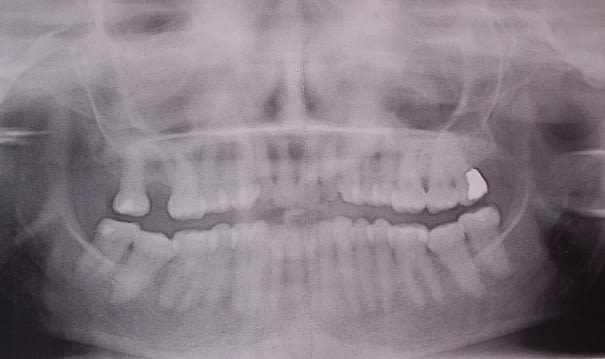

Bon algi, balances nous la pano!!

On peut deviner ce scénario sur des tomos,scanners ou même pano,avec un racourcissement anormal des deux branches montantes et des surfaces articulaires presque horizontales arthrosiques si rhumatisme ou racourcies et arrondies si fracture où les condyles ont été "digèrés" disparus avec le temps.

la pano je l'ai pas encore.... va falloir la lui prescrire et demander un CD pour la poster ici.

Si tu pouvais balancer photos+pano+moulages, je suis comme Humb, impatient de voir...

1/pas de radios exploitables sur le forum

par contre noter la belle clII2 en béance sur les photos "en vrai", étonnant non?

je me trompe peut-être mais tu dis qu'il n'y a que contact sur les dents de sagesse,il me semble pourtant que sur la photo il y a contact en bout à bout de la 13 avec l'antagoniste qui a l'air de faire barrage à une bonne occlusion??